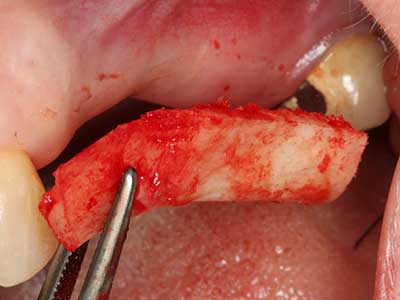

Автогенни костни присадки се използват под формата на блокчета, миди, пръстени и се комбинират с костозаместителни материали като стърготини. Ако имплантното ложе се обработва едновременно с аугментацията, различни системи за филтриране на кост са доказали своята ефективност за събиране на получените костни стърготини. В алтернатива, имплантното ложе може да бъде подготвено с апарат с ниски обороти без охлаждане. Ако не се постави имплант, костните стърготини от периферията могат да бъдат събрани с канюла за събиране на костен материал. Това също е възможно с пиезохирургия, използвайки специални накрайници, които събират костни стърготини с високо качество, в сравнение с костните стърготини, събрани с кръгли борери, както бе потвърдено в научно изследване, сравняващо двата метода (Chiriac, Herten et al. 2005).

Пиезохирургията има допълнителни предимства при събиране на костни блокове. В допълнение към високата прецизност при остеотомията, описана по-горе, употребата на фините режещи накрайници значително намаляват загубата на материал. Голяма загуба на материал по време на събиране може да се очаква с дебелите накрайници, особено при употреба на борери Линдеман (Lakshmiganthan, Gokulanathan et al. 2012). Базалното разделяне, което е необходимо, особено за присадка на блок при ретромолар, е улеснено от специално създадени правоъгълни триони. В резултат на това, пиезохирургията е разглеждана като прецизна, улеснена и безопасна процедура за събиране на костни блокове в ретромоларното пространство (Happe 2007) (Фиг. 1-12).